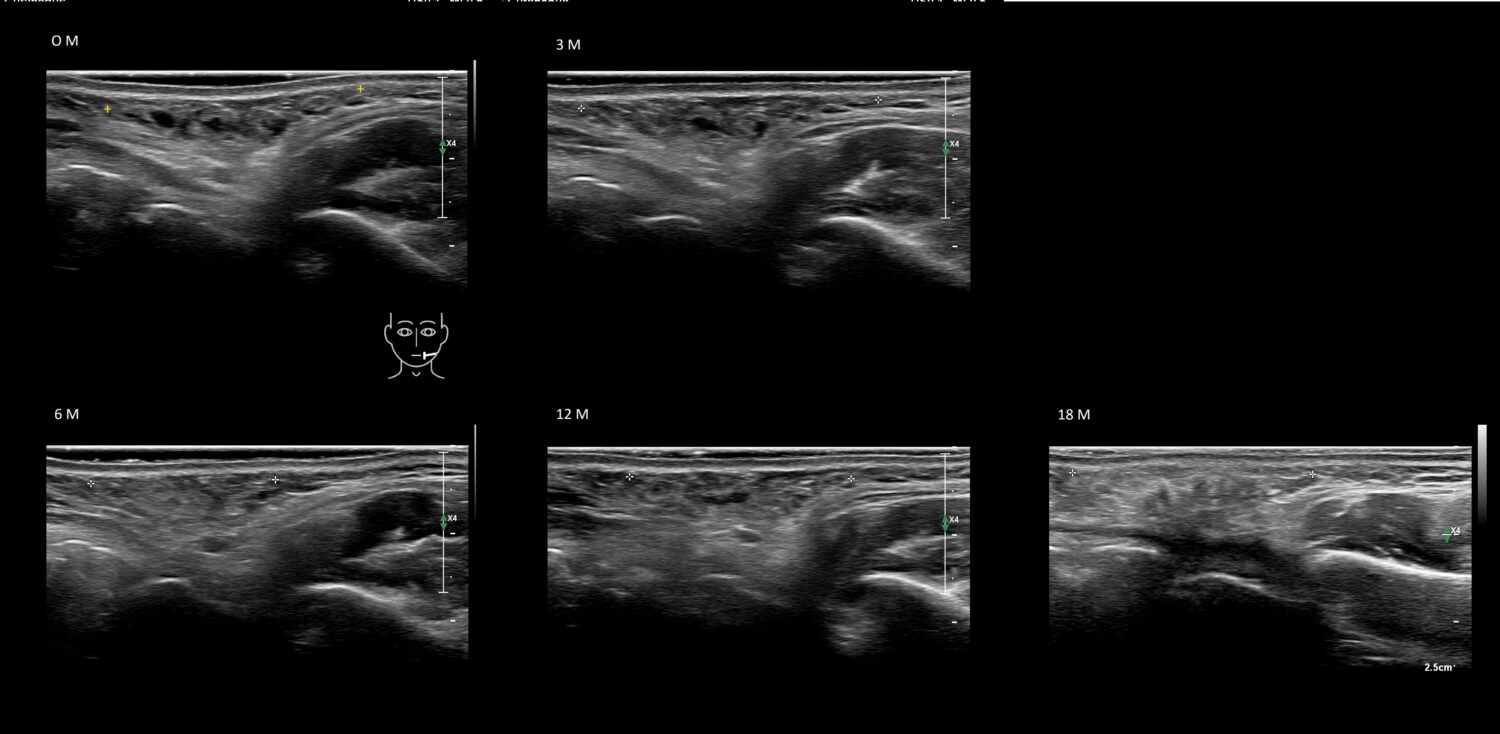

Fillers

Draw in the second image below where the fillers are located. To check if your answer is correct, swipe the first image to the right.